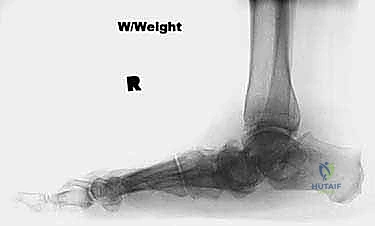

FIG 3 • Radiographs of a 56-year-old diabetic woman with severe pes planovalgus deformity and gross subluxation of the subtalar and transverse tarsal joints radiographically.

Standard weight-bearing radiographs of both the foot and ankle are critical in evaluating severe pes planovalgus deformities. The foot films will determine the amount of subluxation or dislocation of the subtalar and transverse tarsal joints that must be corrected. They can also determine whether there is deformity or bone loss that demands the addition of structural bone grafts. The ankle radiographs are required to confirm that the severe heel valgus is isolated to the hindfoot. Occasionally, severe valgus hindfoot deformity leads to increasing deltoid ligament incompetence, creating a valgus tilt of the talus within the ankle mortise. Deltoid ligament incompetence and valgus tilt of the ankle may necessitate surgical correction of the ankle as well should hindfoot realignment with triple arthrodesis fail to rebalance the tibiotalar joint ( FIG 3 ).

FIG 4 • After single-medial-incision triple arthrodesis, the patient shown in Figure 3 had excellent correction of her deformity without wound-healing complications.